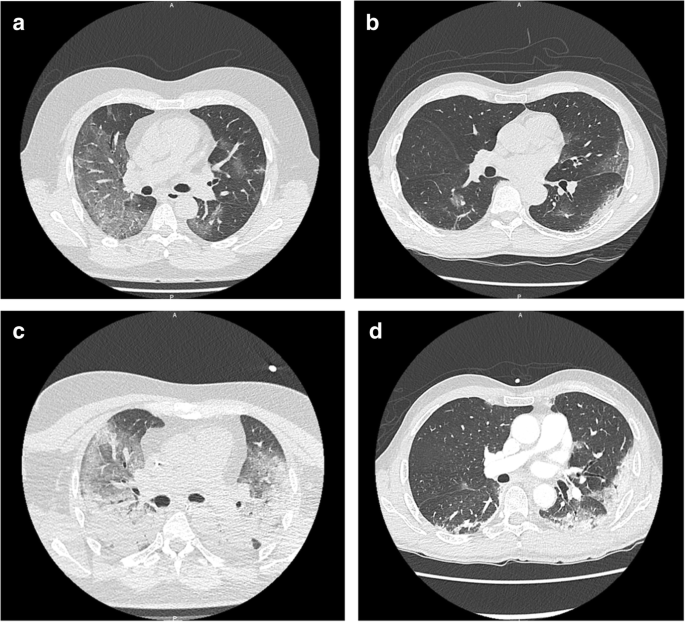

Twenty-six COVID-19 patients were included in this prospective study (13 with ARDS and 13 with moderate pneumonia). Representative CT scans are shown in Fig. 1 and their demographic and baseline characteristics in Table 1. Importantly, there was no difference in demographic characteristics, including comorbidities classically associated with COVID-19 severity, nor was there any difference in duration of symptoms before inclusion between the two groups of patients, thus making it possible to focus our analysis on the biological parameters related to COVID severity. Complete clinical characteristics at day 0, day 4 and day 7 are summarized in the supplementary Table 2.